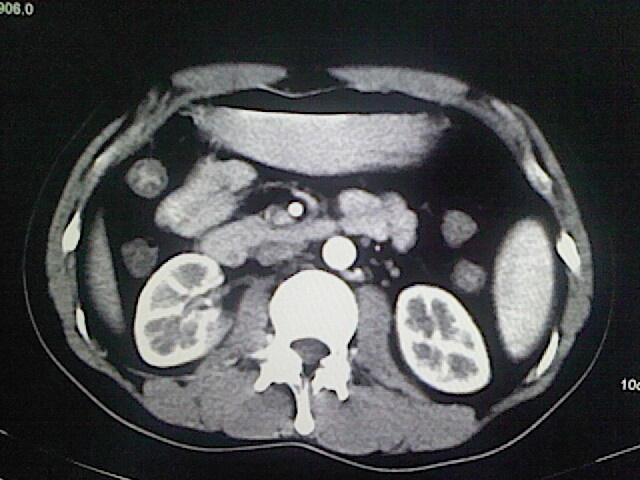

以下是引用卜一在2009-3-14 9:49:00的发言:[br]胆囊萎缩,胆囊壁不规则增厚,内部结构模糊,增强明显强化。另:肝左叶外侧段肝囊肿。支持:慢性胆囊炎!高度可疑:胆囊癌!

以下是引用余辉在2009-3-14 8:48:00的发言:[br]1)慢性胆囊炎。2)肝左叶外侧段肝囊肿。3)脂肪肝。[br]支持,胆囊萎缩,密度增高,不知b超具体有何提示,钙胆汁?结石?

以下是引用jiangjing在2009-3-14 10:18:00的发言:[br]1)慢性胆囊炎。2)肝左叶外侧段肝囊肿。3)脂肪肝。4.】建议行肝功能检查